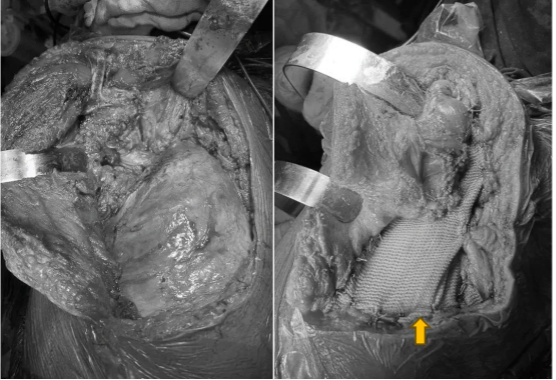

图示:术前X线检查,左侧肩胛骨周围软组织增厚,似肿瘤影

图示:上肢CTA,以左侧前锯肌为中心可见软组织肿块,约118*63*163mm。左侧锁骨下动脉及也动脉分支参与供血